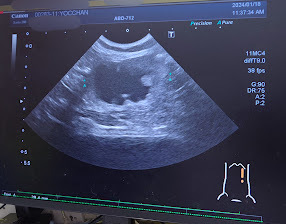

再度、処方してもらった別の抗生物質をかかりつけの動物病院にもらいに行き、それから1週間後に外注検査に出していた薬の検査結果が届きました。判定のところにRと書いてあるのはもう耐性がついていて使えない薬で、Sと書いてあるのがヨッちゃんが効く薬だそうです。

毎日1日2回の抗生物質を10日間頑張って飲み切った後に、1/18(木)にかかりつけの動物病院に腎盂腎炎の経過観察で受診しました。

🐈血尿が出た時は潜血3+だったけど、今回はマイナスになっていて一安心しました。🐈

🐈血液検査も白血球の数値が下がっていて、腎臓の数値も悪くなくてこちらも一安心の結果でした。🐈

🐈腎臓と腎盂は相変わらず肥大したままでしたが、現状維持といった感じなのかなと思います。

とりあえず腎盂腎炎の症状は治っていたので良かったです。🐈